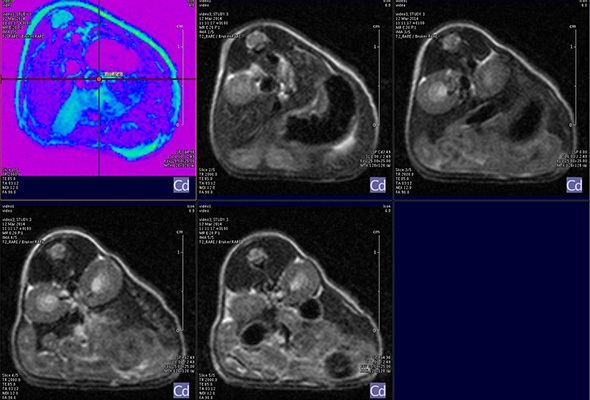

MRI is based on NMR Spectroscopy, which is the best language to talk to nature. We know how it is important to exploit different field strengths in order to extract maximum information from the system that we are investigating.

I think that also the low-field, let’s say the low/intermediate field to work at the 1 Tesla for instance as in the case of this beautiful Icon system, this gave us unique possibilities. Anytime we use a gadolinium-based agent or more in general a paramagnetic basic agent the best field is the 1 Tesla.

So, we can show that there is a real advantage of working at 1 Tesla in comparison to for instance 7 or 9 Tesla when one is using a relaxation enhancer to target a specific epitope in the region of interest.